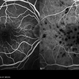

Scanning laser ophthalmoscope

Heidelberg Spectralis - Description

- A fluorescence angiogram of a 40-year-old-man with a Behcet's Disease on his both eyes.